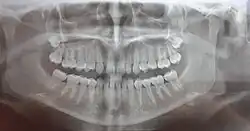

Galería de imágenes